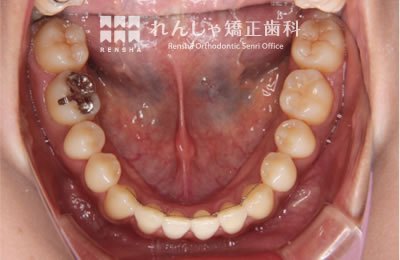

成人

歯列のサイズや形態を大きく変更することができませんが、歯列が極端に狭くなっている場合や、奥歯が前方に移動し前歯ががたついているケースでは、歯列の拡大や奥歯の後方移動を行うことで永久歯を抜歯せずにがたつきを改善できることがあります。このような場合はアライナー型(カスタムメイド)矯正(歯科)装置も治療の選択肢として有効です。

治療中

→

治療後

| 主訴 | 前歯のがたつき |

|---|---|

| 診断名 | Angle Class I 叢生 |

| 初診時年齢 | 18歳8か月 |

| 装置名 | マウスピース型カスタムメイド矯正歯科装置(製品名インビザライン・完成物薬機法対象外) |

| 抜歯非抜歯 | 非抜歯 |

| 治療期間 | 1年2か月 |

| 費用の目安 | 約55万円+消費税(検査料金、都度の処置費用等も合わせた総額) |

| リスク副作用 | 歯の移動に伴う軽微な歯根吸収、歯槽骨吸収、歯肉退縮(いずれも本症例ではほぼ無し)、矯正器具装着中のカリエスリスク増大(本症例ではカリエス発生無し) |